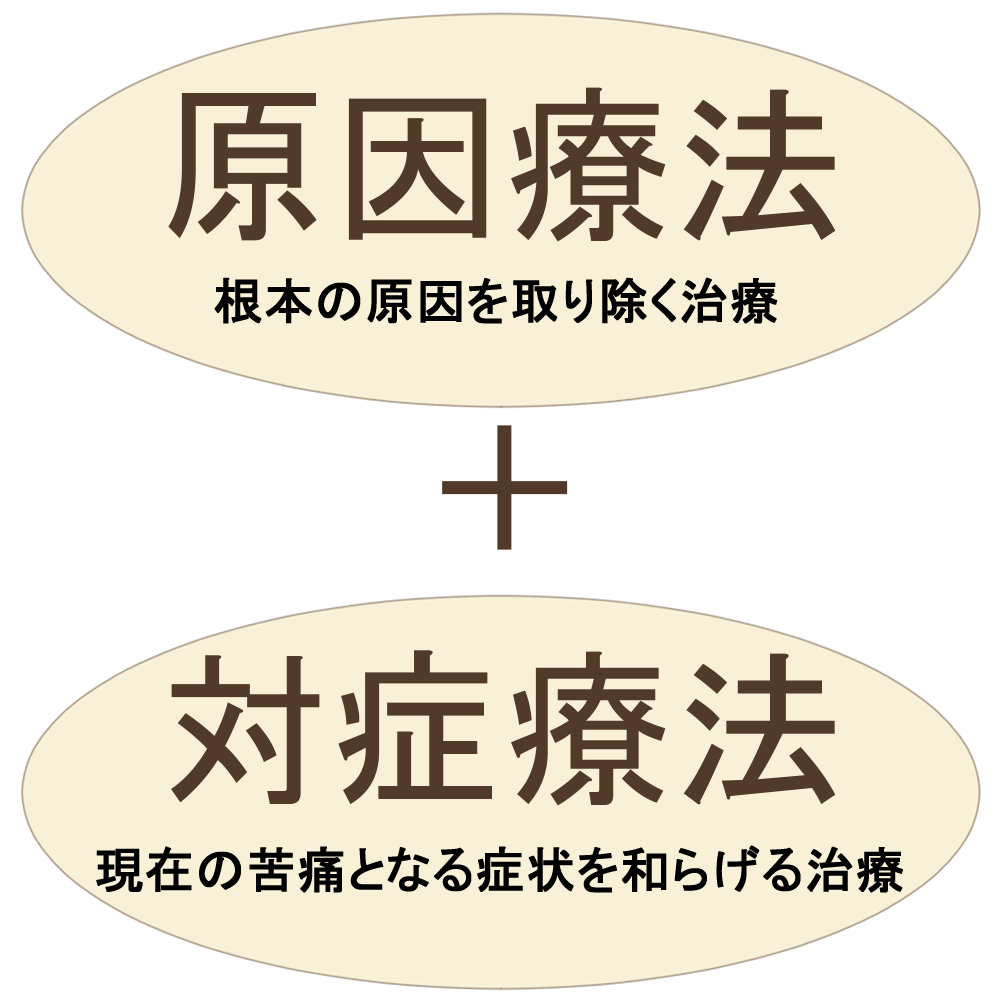

施術は主に2種類あります。1つは一時的に痛みを取ること《対症療法》です。

もう1つは病気の原因をなくすこと《原因療法》です。

一般の整体・鍼灸院は前者《対症療法》に当てはまり、通うことをやめた途端、治療前の状態(体調)に戻ります。後者《原因療法》は難易度が高く病気の原因を特定し、特に原因が生活習慣の症状であれば時間をかけて施術する必要があります。

病気の原因を取り除く《原因療法(根本療法)》が重要視されがちですが、現在の苦痛となる症状を和らげる対症療法も欠かせません。